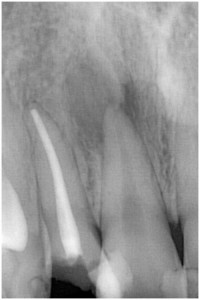

歯髄壊死 右下の前歯 川口の歯科 歯医者 さかえ歯科クリニック

2014年12月16日